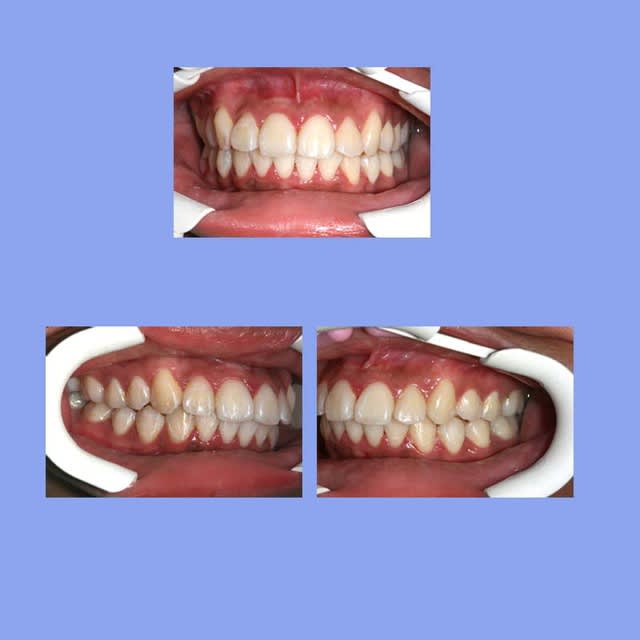

1 e3acmi - Eugenol

2 xg9czy - Eugenol

3 koixmk - Eugenol